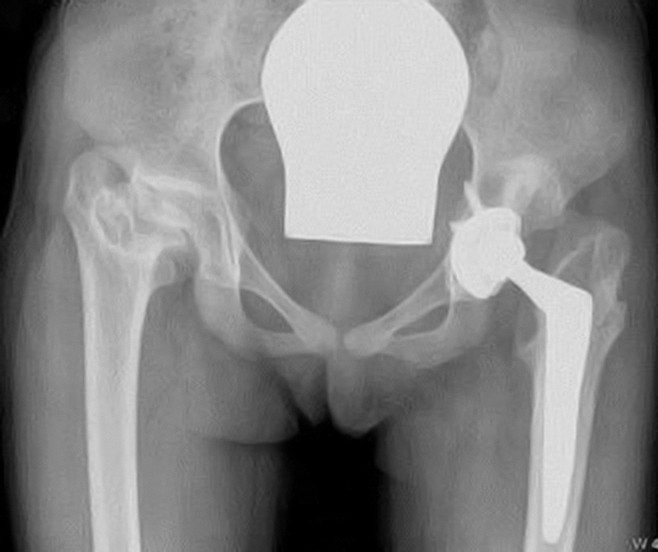

Slik vi ser det, må konservative tiltak, inkludert fysioterapi, være prøvd i noen måneder før pasienten henvises til kirurgisk vurdering. Henvisningen bør inneholde fyldig dokumentasjon om tidligere undersøkelser og behandling. Våre anbefalinger fremkommer i ramme 1. Dersom pasienten har hoftedysplasi med eller uten subluksasjon og uten artroseforandringer, bør takplastikk eller periacetabulær osteotomi vurderes. I de tilfellene hvor hofteleddets bæreflater er ødelagt, kan det være indisert med proteseinnsetting også hos pasienter under 21 år (figur 4). Prosessen som fører frem til en slik indikasjonsstilling, er krevende. Pasienten bør inngående og ved gjentatte konsultasjoner informeres om hva man kan forvente av operasjonen og risikoen for fremtidig revisjonskirurgi. I spesialistkonsultasjonen bør det være både en protesekirurg og en barneortoped som kjenner pasienten. Pasientene må kontrolleres jevnlig etter operasjonen, da det er vist at de unges proteser kan ha bekymringsfulle røntgenologiske slitasjetegn uten at symptomene er alvorlige (14).